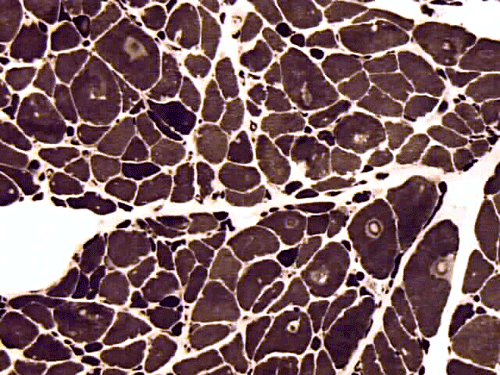

Physical examination revealed weight loss, weakness of arms, and stiffness of joints. He showed no cognitive deficiency and had normal cerebellar function. Muscles in the arm and hands were atrophic. He had significant weakness of upper extremities and the muscle strength is 2/5 in deltoid, 3/5 in biceps and triceps, and 3/5 in brachioradialis, 3/5 in wrist flexion and extension. He had ulnar palsy in hands for over 10 years with the left side more affected than the right. Significant weakness in the muscle of the hands was also noted. There was no pain in the shoulders on palpation. Muscle strength in lower extremities was 5/5 in all muscles except for 4/5 in iliopsoas. The patient could squat up and down without much difficulty. Sensory functions were intact in proprioception and light touch. There was bilateral decrease in pinprick below the knees. Reflexes were trace in upper extremities and were 2/4 knee jerk and 1/4 ankle jerk. There were no pathologic reflexes. The functions of cranial nerve II to XII were intact. There was good, function in the sternocleidomastoid muscles, but atrophic latissimus dorsi, trapezius, infraspinatus and supraspinatus muscle. He had percussion tenderness of his bilateral ulnar cubital tunnels and right median tunnel. Cervical and lumbar spines had full range of movement and were nontender. CT scan of C-spine showed spondylosis in C3-7. Head CT showed mild brain atrophy. Electromyogram and nerve conduction studies of upper extremities were reported as suggestive of motor axonopathy. Laboratory studies demonstrated slight elebation of rheumatoid factor to16.3, the sedimentation rate was 13, creatine kinase in serum was 171, and Lyme’s test was negative. A muscle biopsy was perform as part of his workup. Representative photos from the muscle biopsy are shown below:

All stains and histochemistries are performed on frozen materials.

On hematoxylin-eosin stained sections, there is an increased variation of fiber diameter with many atrophic fibers intermingled with fibers of normal caliber. There is no evidence of fiber grouping or perifascicular atrophy. No inflammatory cells are present. There is also mild interstitial fibrosis (Panel A). On higher magnification, many fibers have a round concentric structure (Panel B). Irregular, centrally located depositions are also identified on modified Gomori's trichrome. The concentric nature, however, is not as obvious as in the hematoxin-eosin stained sections (Panel C). Type I and II fibers are not clearly separated in the ATPase preparation at pH 9.4. This is a common situation in chronically ill muscle (Panel D). The type I fibers are unusually dark. There is an increase in the proportion of type I fibers. The atrophic fibers are usually type II fibers. The concentric lesions are found predominantly in type I fibers (Panel E). There is an increase in PAS staining which is consistent with increased glycogen storage (Panel F). No increase in lipid content is demonstrated by oil red O (Panel G). On NADH-TR reaction, the concentric structures appear to have a clear central core that is devoid of enzymatic activity, a rim with intense enzymatic activity and a surround zone with relatively normal reactivity. These features are classic for target fibers (Panel H and I). No deficiency of laminin-2 (merosin) (Panel J) or dystrophin (Panel K) is demonstrated by immunohistochemistry. The central lesions are also immunoreactive for both laminin-2 and dystrophin. Immunohistochemistry for desmin demonstrate a core of strong immunoreactivity and also strong reaction in the sarcoplasmic membrane (Panel L and M). The target structures are also well demonstrated on semithin sections (Panel N). On electron microscopy, z-disc streaming is a common finding and they are often admixed with a substantial amount of dense granular electron dense substance (Panel O and P). There are also numerous cytoplasmic bodies characterized by radiating intermediate filaments (spheroid bodies) (Panel Q and R).